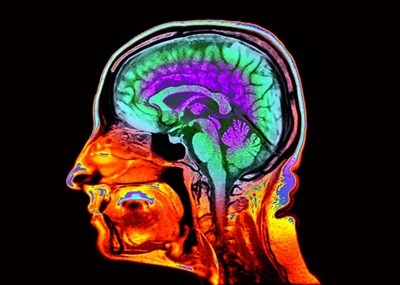

Credit: Cavan Images/Getty

Some sex differences in brain-connectivity patterns become more pronounced with age, according to new research.

In their study, Kuceyeski and her colleagues set out to investigate sex-linked variation in brain development by analysing functional magnetic resonance imaging brain data from 1,286 people, half of whom were male and half female. The scans captured a snapshot of each individual’s brain age, but did not follow the same people throughout their lives. The analysis was based on sex at birth because the researchers didn’t have data on the participants’ gender identities.